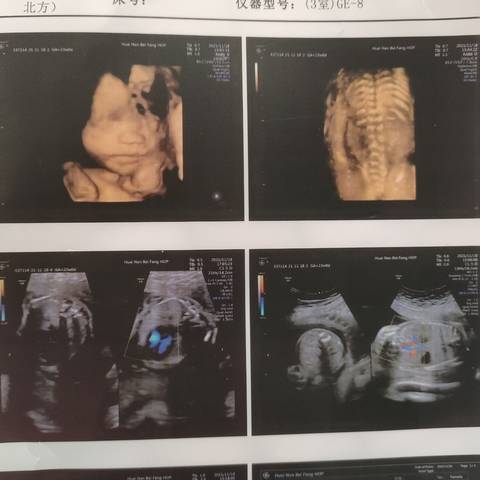

24周四维,帮我看看是男宝还是女宝?谢谢!

journal_insert_pic_1676073520journal_insert_pic_1676073549journal_insert_pic_1676073577

你好。我们是判断不了男宝宝跟女宝宝的,孕期定期检查,我觉得宝宝健康就好的。祝心想事成 。